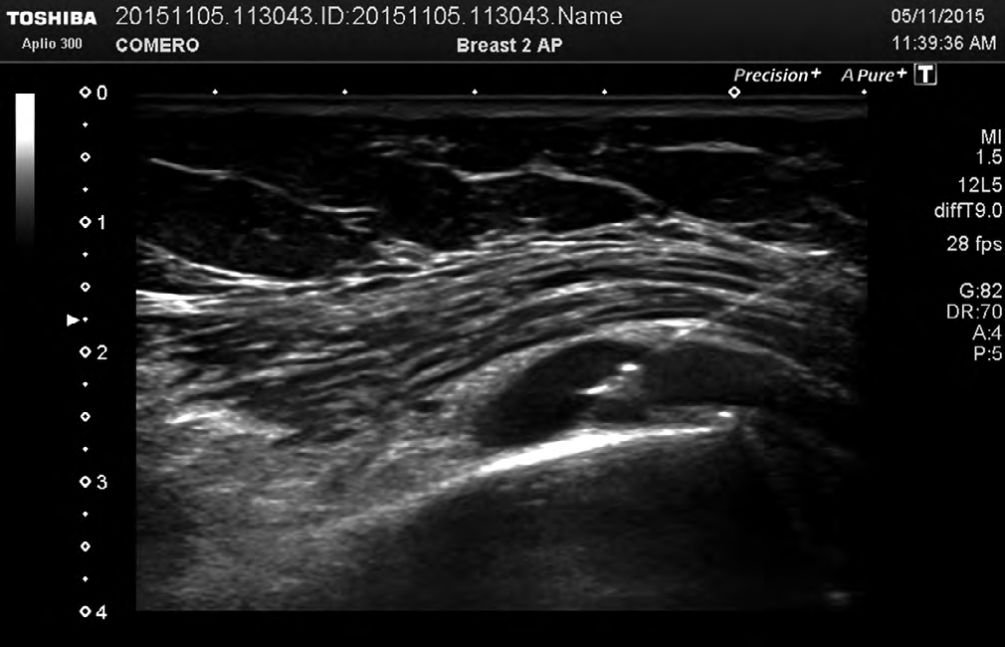

Foto 3

Punta de la aguja dentro de la articulación. Se eligió el abordaje en forma transversa. Como se ve, es una articulación pequeña, por lo que se debe administrar escasa cantidad de fármacos. Luego del procedimiento se indicó a todos los pacientes reposo funcional de la articulación por 48 horas.

Finalmente, para la articulación ACC, también en decúbito supino, se ubicó el transductor transversal o paralelo a la articulación, de manera para poder observar el extremo de la aguja al penetrar en la cápsula articular. (5-11)